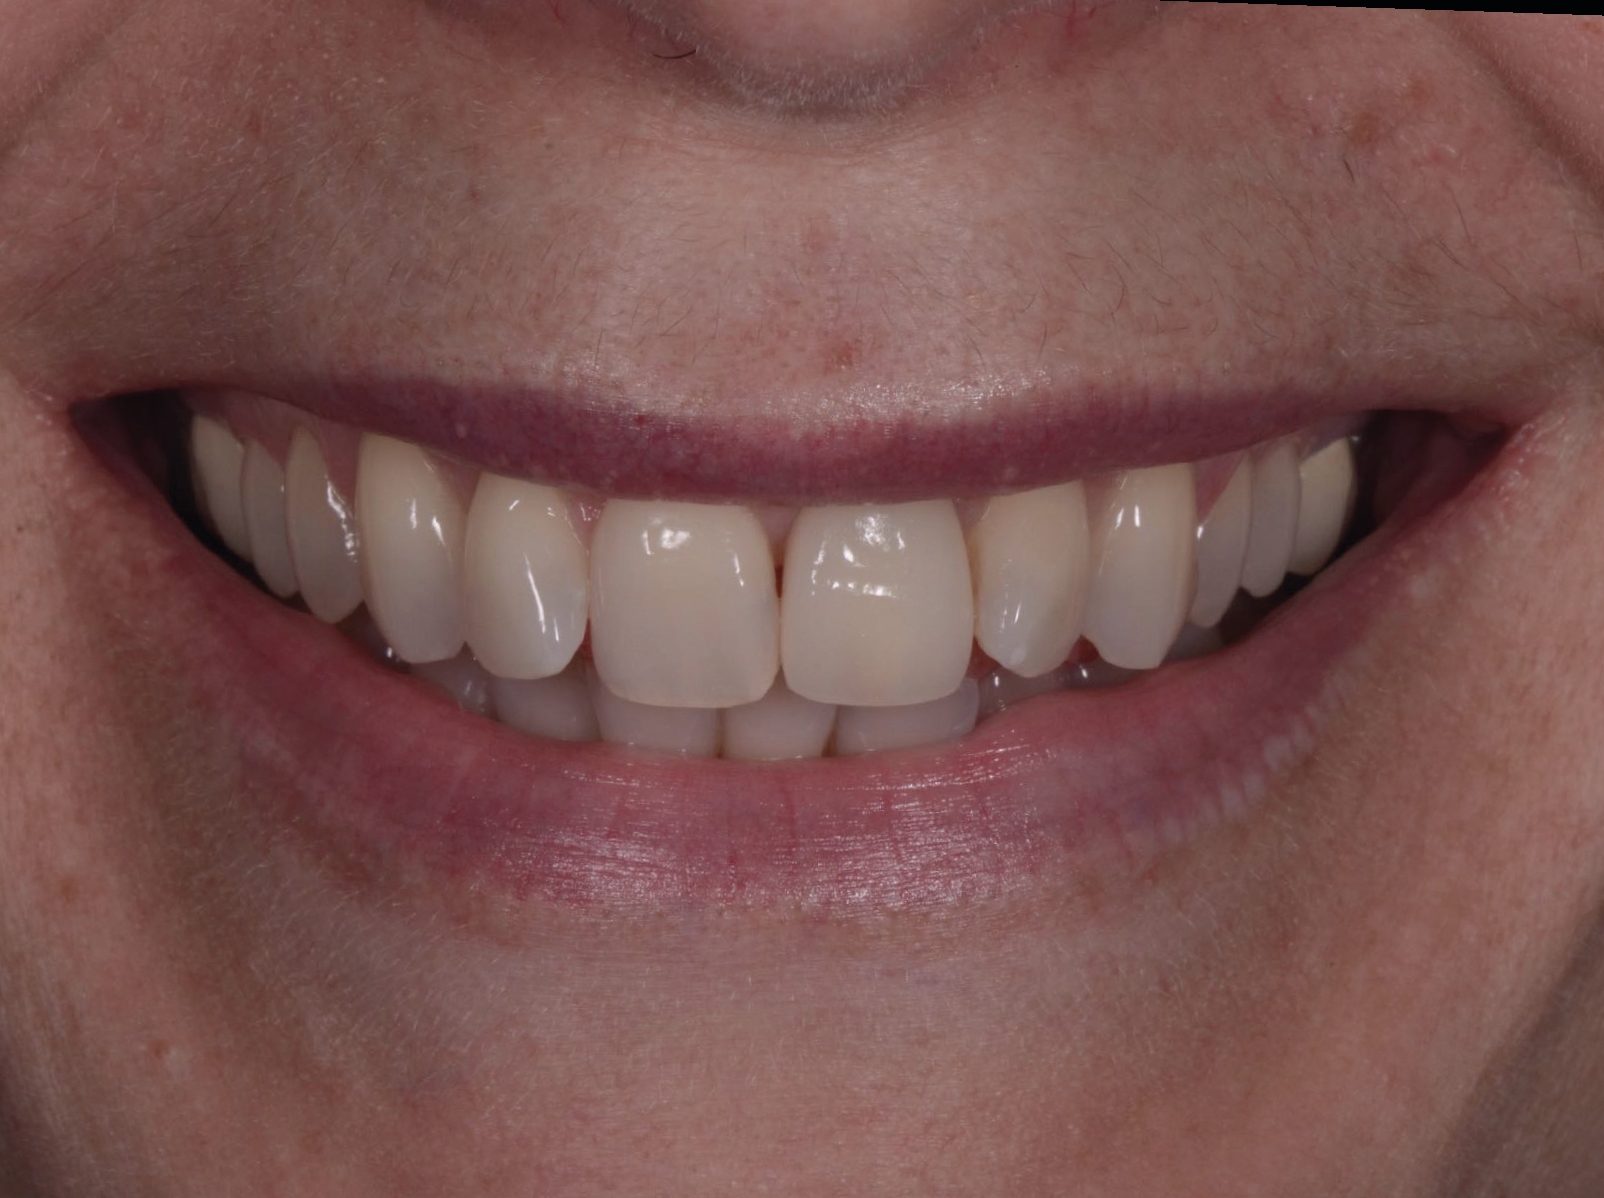

Une patiente de 42 ans est adressée au cabinet pour le remplacement de son incisive centrale supérieure gauche (dent 21) qui est à l’origine de douleurs. Un antécédent de traumatisme dentaire remontant à l’adolescence est rapporté. La ligne du sourire de la patiente est normale, mais la dent 21 est égressée (Fig. 1) La gencive présente un biotype raisonnablement épais et le feston gingival est très marque.

Fig. 1a : Vue préopératoire extraorale : lèvres au repos a

Fig. 1b : Vue préopératoire extraorale : lèvres au sourire

Fig. 21a : Sourire avant le traitement.

Fig. 21b : Sourire après le traitement.

Lors du suivi a cinq ans, on ne peut que constater le résultat esthétique maintenu (Fig. 21). La radiographie montre un niveau osseux stable et une connexion étroite entre l’implant et le pilier (Fig. 22).